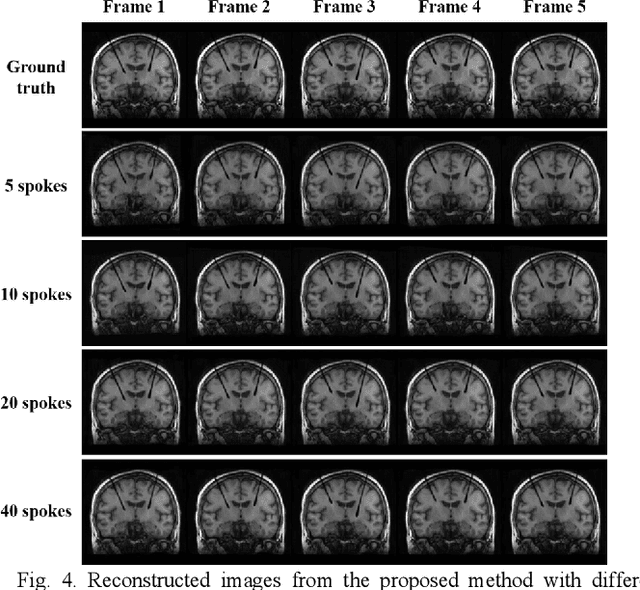

Abstract:Interventional magnetic resonance imaging (i-MRI) for surgical guidance could help visualize the interventional process such as deep brain stimulation (DBS), improving the surgery performance and patient outcome. Different from retrospective reconstruction in conventional dynamic imaging, i-MRI for DBS has to acquire and reconstruct the interventional images sequentially online. Here we proposed a convolutional long short-term memory (Conv-LSTM) based recurrent neural network (RNN), or ConvLR, to reconstruct interventional images with golden-angle radial sampling. By using an initializer and Conv-LSTM blocks, the priors from the pre-operative reference image and intra-operative frames were exploited for reconstructing the current frame. Data consistency for radial sampling was implemented by a soft-projection method. To improve the reconstruction accuracy, an adversarial learning strategy was adopted. A set of interventional images based on the pre-operative and post-operative MR images were simulated for algorithm validation. Results showed with only 10 radial spokes, ConvLR provided the best performance compared with state-of-the-art methods, giving an acceleration up to 40 folds. The proposed algorithm has the potential to achieve real-time i-MRI for DBS and can be used for general purpose MR-guided intervention.